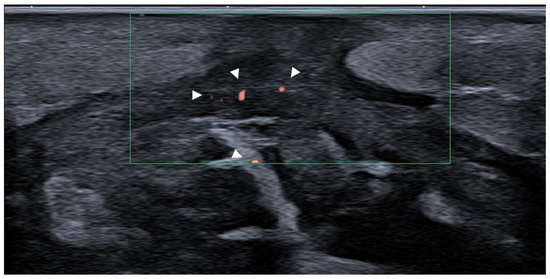

Fasciitis

- Nakagomi, D. Power Doppler ultrasonography findings of eosinophilic fasciitis. Rheumatol. Adv. Pract. 2024, 8, rkae067. [Google Scholar] [CrossRef] [PubMed] [PubMed Central]